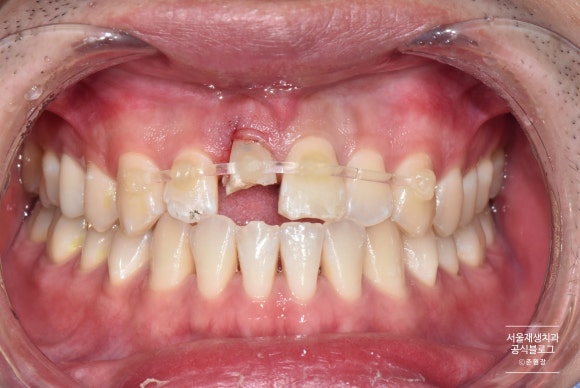

치료 전

어젯밤에 넘어졌어요. 지금은 아프지 않아요.

사고 다음 날 내원해주셨습니다.

사고 당시에는 병원에 방문하지 않으셨다고 하셨습니다.

다행이라고 해야할까요, 치아의 위치가 달라지는 일 없이 파절로만 끝났습니다.

사진을 같이 살펴볼까요?

앞니의 심한 파절과, 인접 치아들의 작은 파절들이 관찰됩니다.

심하게 파절된 치아는 파절선이 잇몸 깊게 내려가 있었습니다.

자칫 발치로 이어질 수 있는 케이스였지만,

나이가 젊으신 환자분이어서 가능한 자연치아를 유지하게 해드리고 싶었습니다.

따라서, 신경치료 후 포스트 식립 및 크라운 치료를 계획하였습니다.

치아 고정 및 신경치료 진행

크던 작던 외부의 충격을 받은 치아는 일시적으로 흔들릴 수 있습니다.

치아의 흔들림을 최소화하여 다시금 안정적으로 자리잡게 해주기 위하여 치아 고정을 시행합니다.

사례에 따라 다르지만, 대개 2주 정도 고정장치를 부착합니다.

앞니의 신경치료를 끝내기엔 충분한 기간이지요.